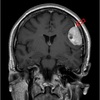

Que arteria se encuentra afectada

A

PICA